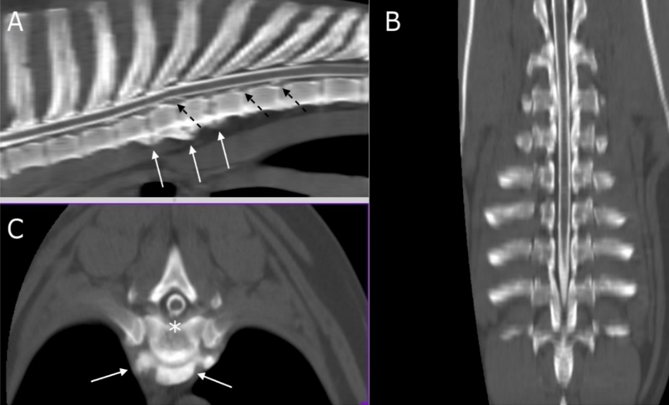

Figure 1: multi-planar reconstruction (MPR) of CT myelography scan on sagittal (A), transverse (B), and dorsal (C) planes. White arrows indicate from T4 up to T7 (A) and at the level of T5-T6 (B) ventral spondylosis. Asterisk shows the disc protrusion in T5-T6 (B) while dashed black arrows (A) indicate multiple disc protrusions in T7-T8 and T8-T9.

This was confirmed as generalized disc degeneration using MRI (Figure 2), at sites T3-T4, T5-T6, T7-T8, T8-T9, T13-L1, and L1-L2, without compressions or signal changes of the spinal cord (Figure 1C, 3B, 4B-C and 5). Widening of the epidural and subarachnoid space was noted (Figure 4 B-C); this alteration was considered secondary to reduced transverse diameter of the spinal cord. CSF was normal on examination. After 23 months, a new MRI was performed using a 0.3T unit (Hitachi Airis II), with turbo spin-echo T2 weighted imaging (TSET2WI= TE 120, TR 5000, and Nex 4), spin-echo T1 weighted imaging (SET1WI= TE30, TR448, Nex 2), and short tau inversion recovery (STIR= TE 25, TI 110, TR 6000, and Nex 2) in the sagittal and transverse planes, confirming the previous findings.

The MRI scan confirmed the presence of the protrusions already detected in previous imaging studies. Disc protrusions were still low and were not significantly compressive, and the spinal cord had a normal signal; however, the reduced diameter and intra-canal free space were mostly filled with epidural fat ventrally and laterally on the left side of the spinal cord. These findings were confirmed using necropsy (Fig 6A). The segment of the spinal cord between T5 and L7 (Fig 6B) was histopathologically analyzed after fixation in 10 % neutral buffered formalin, followed by paraffin embedding and routine staining of the slides using hematoxylin and eosin.